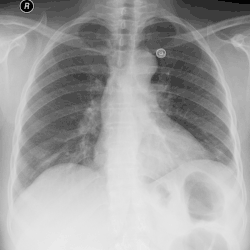

Эмпиема плевры

Эмпиема плевры (пиоторакс, гнойный плеврит) — скопление гноя в плевральной полости (разновидность плеврального выпота)[1]. Как правило, эмпиема плевры развивается в связи с инфекционным поражением лёгких (пневмонией) и часто ассоциирована с парапневмоническим выпотом. Различают три стадии эмпиемы: экссудативная, фибринозно-гнойная и организующая. При экссудативной фазе происходит накопление гноя. Фибринозно-гнойная стадия проявляется осумкованием плевральной жидкости с формированием гнойных карманов. В конечную, организующую стадию, происходит рубцевание плевральной полости, которое может привести к замуровыванию лёгкого[2].

Для хронической эмпиемы характерно формирование симптома барабанных палочек. Отмечается укорочение перкуторного звука и ослабление везикулярного дыхания с поражённой стороны. Для диагностики используется подсчёт лейкограммы, рентгенография и компьютерная томография грудной клетки, ультразвуковое исследование[2].